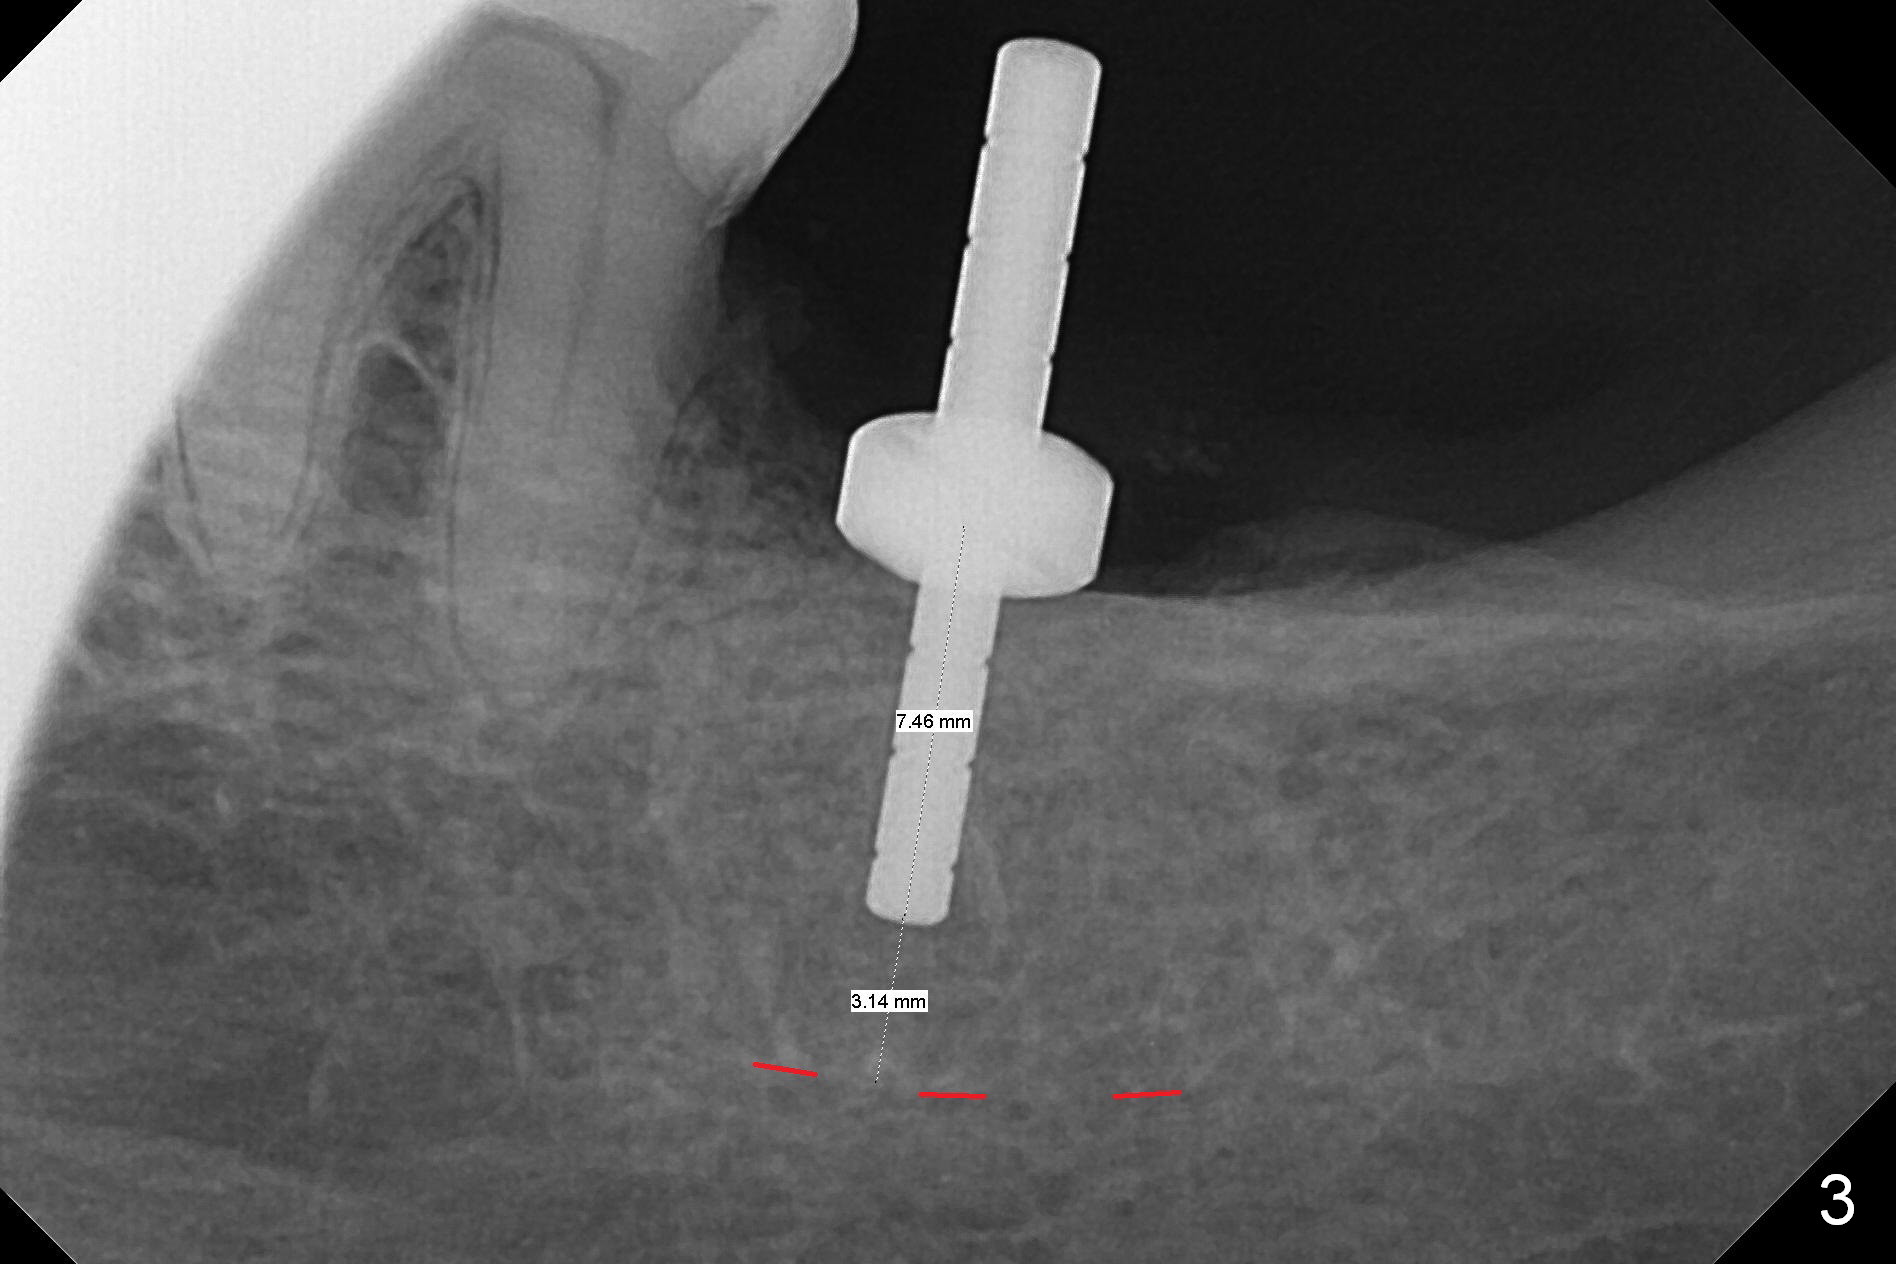

Preop palpation of the edentulous area at #18 does not show the flatness of the ridge top as shown by CBCT. Incision reveals that the ridge is not as wide as CBCT indicates (Fig.1 (coronal section) between arrowheads). In fact the ridge is concave (Fig.2 red dashed line). Osteotomy is initiated in the middle of the concavity (Fig.2 green line) with insertion of 7 mm guide pin (Fig.3). After removal of the pin, the osteotomy is moved buccally (Fig.4). After Marking Bur and 4.3 mm Magic Drill, a 5x9 mm IBS implant is placed with 2.8 mm clearance from the Inferior Alveolar Canal (Fig.6). Following deepening the osteotomy with Final Drill, the implant is placed deeper (Fig.7). The osteotomy happens to be established in the mesial socket, since the distal socket has not completely healed (Fig.6 yellow dashed line). Granulation tissue is removed. Since the lingual crest is lower than the buccal one (Fig.1 B), there is lingual thread exposure after implant placement (Fig.5). The exposed thread is covered by bone graft (autogenous bone, allograft and Osteogen, Fig.5 pink circles). Some of the graft is apparently pushed into the distal socket (Fig.7 yellow dashed line) post GBR and suture. As the implant is placed twice, insertion torque is <10 Ncm (although the implant is stable). A 5x3 mm healing abutment is placed (Fig.7 H).